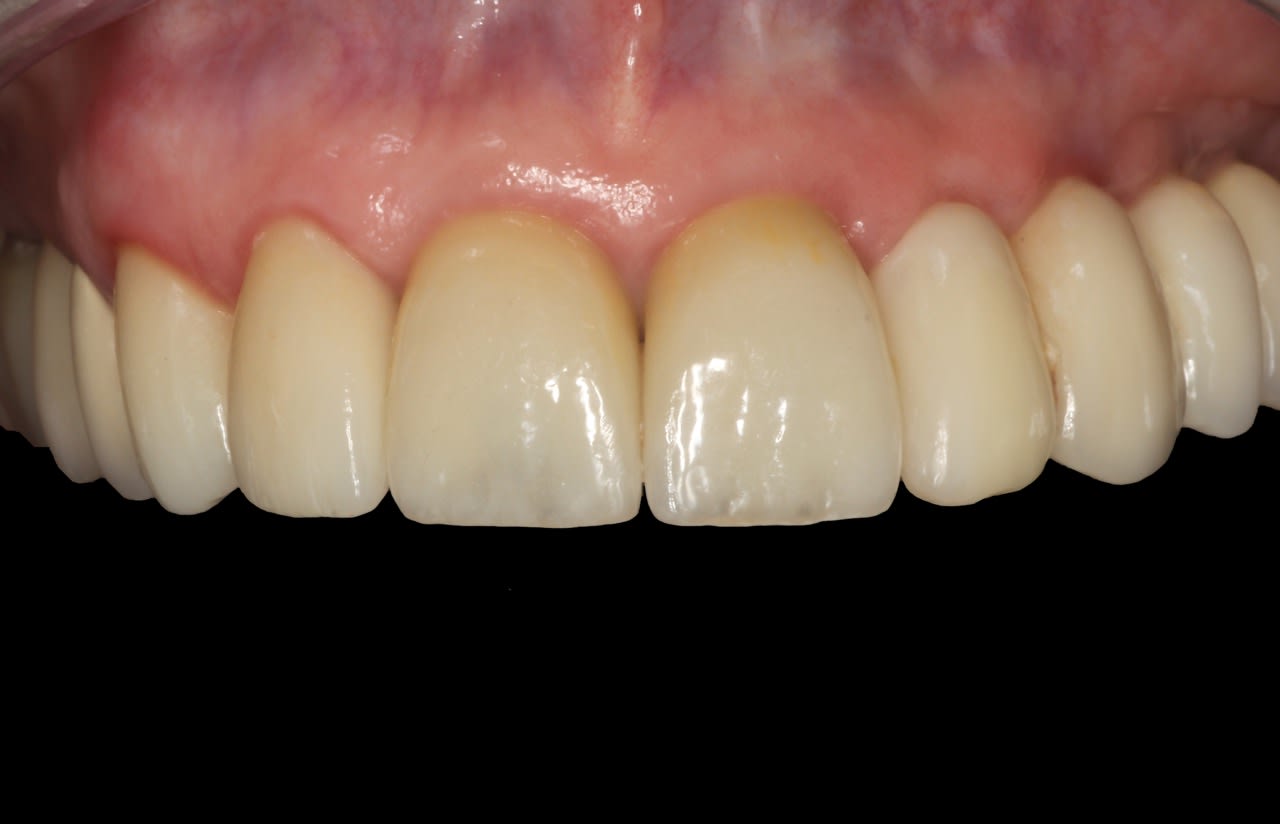

The final impression (closed tray) was obtained in April 2012. The final ceramic crowns (IPS e.max Ceram) and custom porcelain-veneered, regular-diameter (RD) UCLA abutments (Genesis; and Creation CC, Jensen Dental, www.jensendental.com) (Figure 24, shown with PFM crowns and retention screws) were delivered in May 2012. Using a platform-switched connection, the abutments were torqued to 30 Ncm, the access holes sealed with Teflon, and the final crowns cemented with RelyX Unicem. Figure 25 through Figure 28 show the final IPS e.max Ceram crowns from periapical, facial, and incisal views, with a midfacial PD of 3 mm at the 18-month follow-up (Visit 7). A thick biotype is evident in Figure 26, as determined by the inability to detect the outline of the periodontal probe inserted below the restoration’s gingival margin.50 This image also demonstrates an excellent esthetic outcome.

After this visit, additional restorative work was completed on teeth Nos. 6 and 7. Figure 29 and Figure 30 (retracted and smile views, respectively, at 3 years, Visit 8) show the excellent esthetic outcome registered during the 3-year postoperative period.